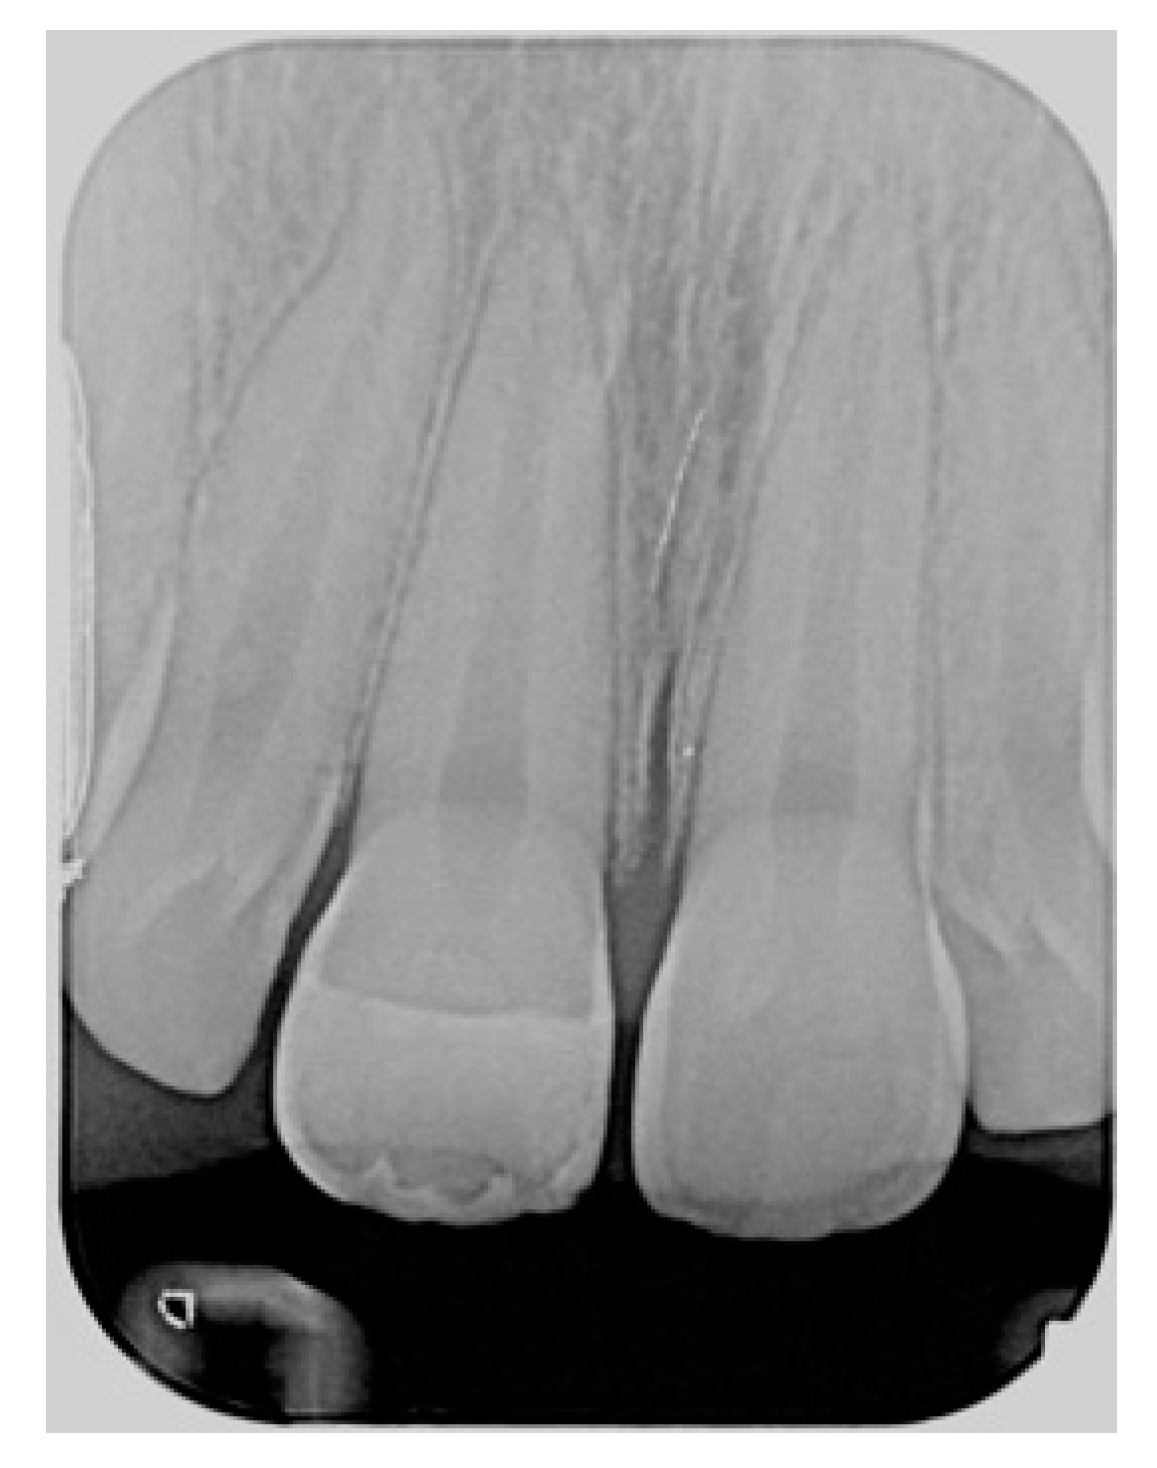

Figure 2.

Initial x-ray. Reprinted from Restauri diretti nei settori anteriori, G. Paolone, S. Scolavino, © 2021, with permission from Quintessence Publishing Italy.